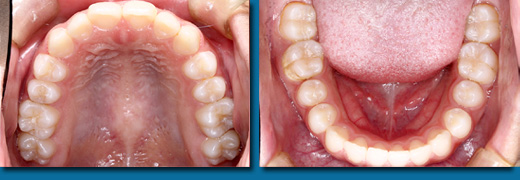

専門的にはう蝕診断といいますが一般の方が思うほど簡単なものではなく、集団検診でも歯科医院でも見逃されることが多くあります。写真の歯はいままで虫歯ではないと言われていましたが冷たいものがしみたり痛みがあったそうです。当院で調べてみると大きな虫歯が中で拡がっていることがわかりました。虫歯の入り口は小さくても中で大きく拡がっていることが多くあります。色々な診査器材を使用して虫歯も虫歯になりやすい歯も見逃しません。